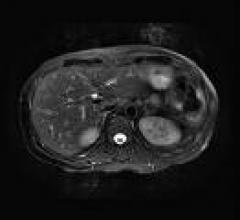

MRI creates images from the magnetic resonance created in hydrogen atoms when they are polarized and an electromagnetic pulse is used to knock them off axis. This section includes MR analysis software, MRI scanners, gadolinium contrast agents and related magnetic resonance imaging accessories.